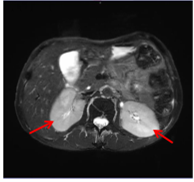

肾脏B超:左肾大小 116×54mm,右肾大小 119×50mm,双肾形态饱满,回声减低且不均匀。

肾脏MRI:双肾增大(下图:红色箭头)。